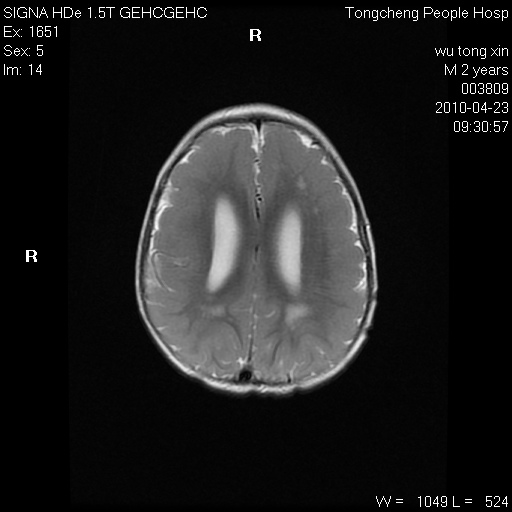

以下是引用赵物学在2010-4-25 12:43:00的发言:[br]巨脑回[br]侧脑室后角低密度影考虑hie或肾上腺脑白质营养不良?[br][br][本贴已被 赵物学 于 2010-4-25 12:51:28 修改过]

以下是引用gaoxiao在2010-4-25 16:54:00的发言:[br]巨脑回畸形。脑白质髓鞘化不良

以下是引用pujunzhi在2010-4-25 21:35:00的发言:[br]考虑 1双侧大脑皮质发育不良 2轻度脑积水 3双侧脑室后角旁片状长t1长t2信号,需继续观察,因为正常小儿此处脑白质的髓鞘化时间可以延迟到4-6岁,才显示正常。